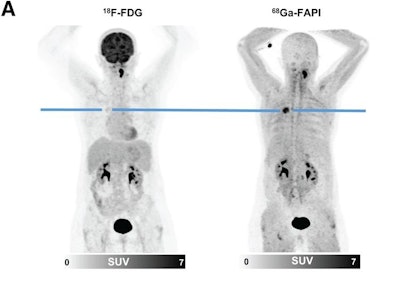

F-18 FDG and Ga-68 FAPI-46 images of a 51-year-old woman with adenocarcinoma with lepidic growth pattern in right upper lobe. (A) Maximum-intensity-projection PET images. The lesion had F-18 FDG uptake below blood pool level but was strongly Ga-68 FAPI-46-positive. CT-guided biopsy led to pathologic diagnosis of adenocarcinoma, and the patient was treated by stereotactic body radiation therapy because of functional inoperability. Image courtesy of the Journal of Nuclear Medicine.

According to the results, Ga-68 FAPI-46 PET scans revealed whether primary lung tumors were malignant (n = 12) or benign (n = 7), with intense Ga-68 FAPI-46 radiotracer uptake seen in tumors in F-18 FDG-negative scans.